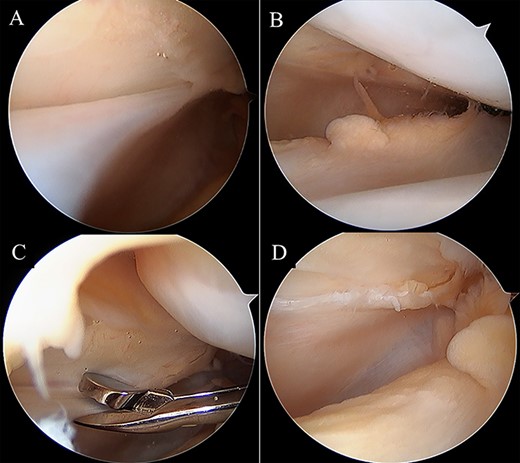

A 16-year-old female with a history of recurrent patellar dislocation underwent MPFL reconstruction surgery (Fig. 1). There was no pain nor tenderness in the medial patella, and the apprehension test was positive before surgery. Preoperative magnetic resonance imaging (MRI) showed no injury to the cartilage in the patellofemoral (PF) joint, and hypertrophic medial plica was observed. Arthroscopy showed no cartilage injury in the PF joint. For the tendon graft, a tape-type artificial ligament with a width of 15 mm (Leeds-Keio Ligament, Xiros plc, Leeds, United Kingdom) was used [2]. A bone tunnel was constructed to pass the ligament through the medial side and anterior surface of the patella, and the folded ligament was pulled into the femoral tunnel and fixed at 60° flexion with a bioabsorbable screw (BIOSURE PK Screw, Smith & Nephew Inc., Endoscopy Division, Mansfield, MA, United States). The tension pattern of the reconstructed ligament exhibited laxity under flexion and mild tension under extension. ROM exercises and partial weight-bearing were allowed at 1 week postoperatively and gradually progressed to full weight-bearing at 4 weeks postoperatively.

Radiographs of the left knee after MPFL reconstruction. Anteroposterior (A), lateral (B) and axial (C) radiographs of the left knee after MPFL reconstruction showing the entry of patella tunnel (white arrow), entry of femoral tunnel (white dot arrow) and bone tunnel of patella (white dot line). Patella tilt of post-operation was similar to that of pre-operation.